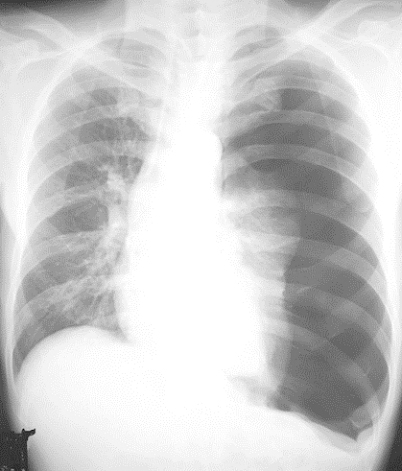

気胸は胸部レントゲン撮影を行えば診断できます。肺の縮みの程度により外来経過観察するか入院加療を行うか決定します。